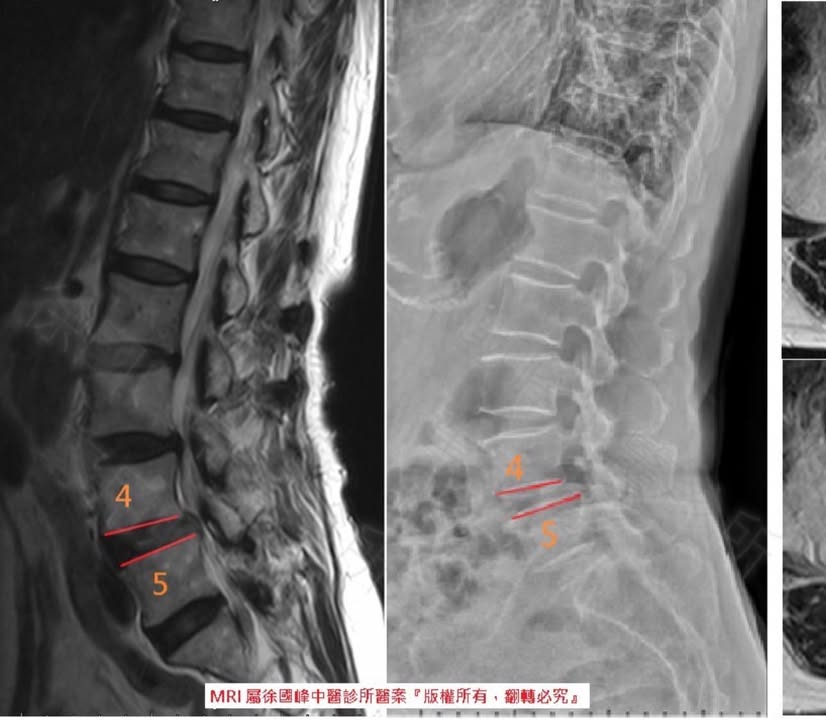

❤️🩹 來看診前,患者自述當初出常痛,而且痛到無法行走,雖然檢查後醫生並無建議用手術的方式處理,但對骨科來說看到林阿姨的MRI後會建議手術來處理,但阿姨本身也沒特別想使用此方式,後來得知親戚有來貴診所治療恢復不錯目前也已畢業,就特別介紹林阿姨來徐醫師這裡諮詢

2.右側L4L5椎體滑脫合併重度椎孔狹窄